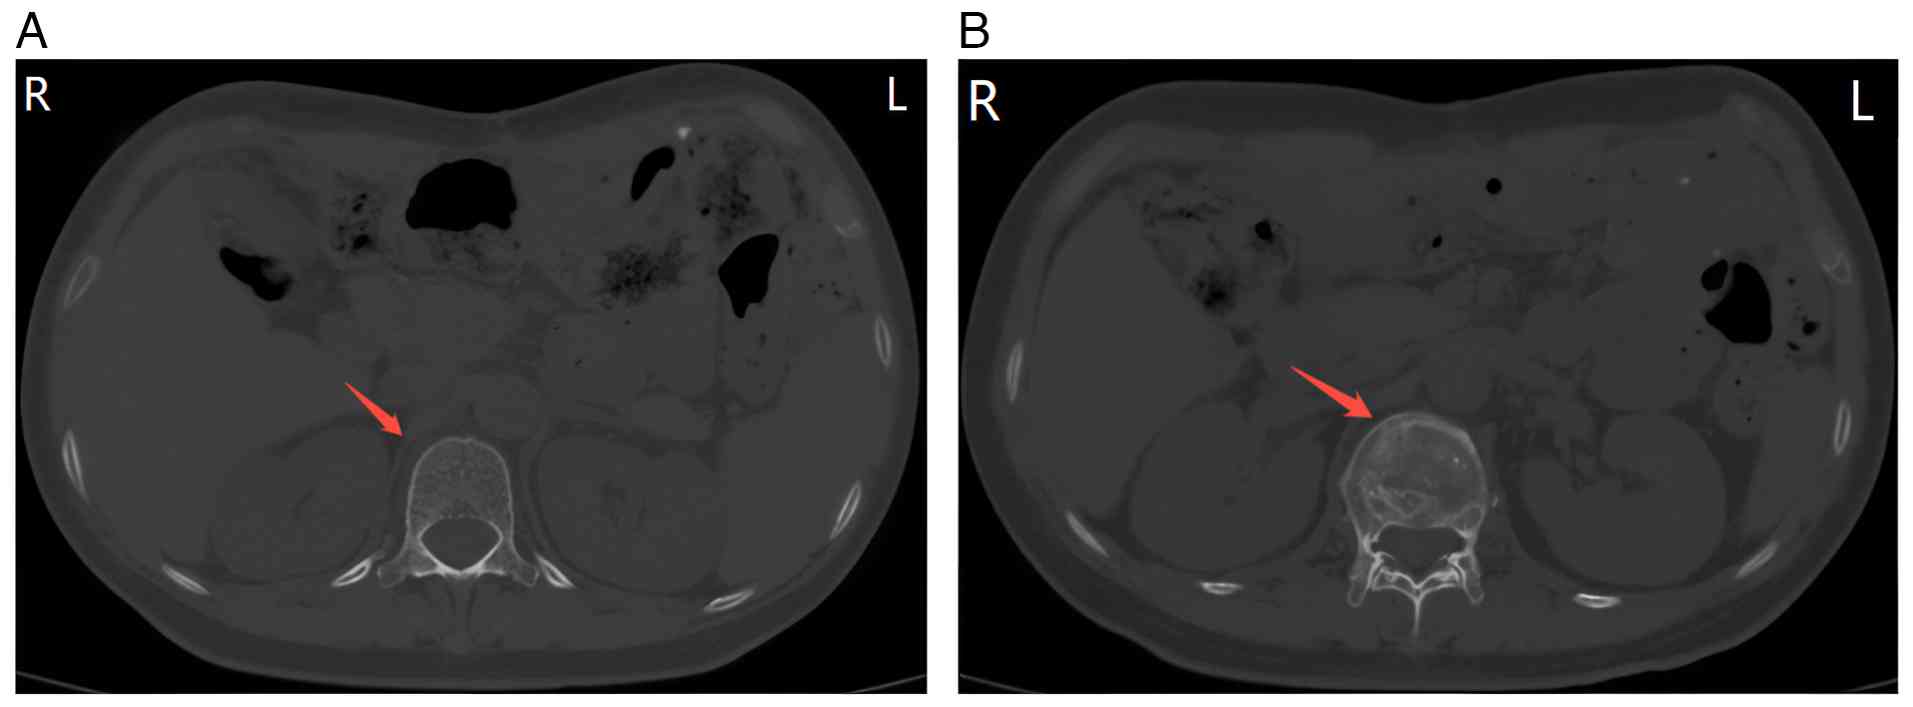

In April 2024, the patient complained of fatigue, poor appetite and lower back pain. The patient was admitted with the discovery of an abdominal incisional hernia during physical examination. Routine blood tests on admission revealed: White blood cells count, 2.15×109/l (reference range, 3.5–9.5×109/l); red blood cells count, 2.37×1012/l (reference range, 3.8–5.1×109/l); hemoglobin, 68 g/l (reference range, 115–150 g/l); and platelets (PLT), 38×109/l (reference range, 125–350×109/l). Anemia-related indicators were: Serum ferritin, 376.0 ng/ml (reference range, 13–232 ng/ml); folate, >24 ng/ml (reference range, 5.21–20 ng/ml; and vitamin B12, 235 pg/ml (reference range, 200–1,100 pg/ml). Tumor markers were: Carcinoembryonic antigen (CEA) 5.5 ng/ml (reference range, 0–6.5 ng/ml); and CA19-9, 133 U/ml (reference range, 0–39 U/ml). Abdominal CT (Fig. 2) showed L1 vertebral compression fracture. Lumbar plain MRI (Fig. 3) showed diffuse reduction of T1 and T2 signals in multiple thoracolumbar and sacral vertebrae. Whole-body bone scan (Fig. 4) (3-h acquisition after 7 mCi 99mTc-DTPA injection) showed diffuse increased bone uptake of imaging agents (‘super-bone scan’), suggestive of multiple bone metastases. The bone marrow aspiration results (Fig. 5) showed images of metastatic tumor cells, indicating tumor recurrence and metastasis. Accordingly, the patient received five cycles of combination regimen [albumin-bound paclitaxel 100 mg (D1,8) and cedilimumab 200 mg (D1), in a 21-day cycle] and supplemented with bone-modifying agent (denosumab 120 mg administered at 4-week intervals). A partial response was achieved following five cycles of therapy, which coincided with a steady recovery of PLT (82×109/l) and a progressive decrease in CEA (1.4 ng/ml) and CA19-9 (36.5 U/ml) levels.

Abdominal plain CT imaging. No

significant abnormalities were observed in the (A) T12 vertebral

body and (B) L1 vertebral compression fracture.

Figure 2.

Abdominal plain CT imaging. No significant abnormalities were observed in the (A) T12 vertebral body and (B) L1 vertebral compression fracture.